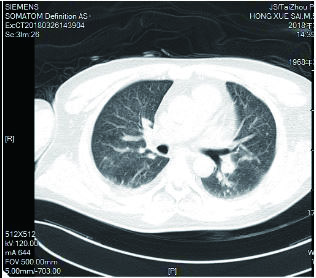

该患者入院后因氧合不能维持、呼吸窘迫直接从急诊收治ICU,大剂量激素冲击及气管插管,呼吸机SIMV+PS模式支持治疗,氧合指数改善不明显,及时行俯卧位通气,但氧合指数仍然小于100,PAO2 38 mmHg, SpO2 78%左右,考虑患者病情危重,且血流动力学不稳,血管活性药剂量大,当天下午行V-V模式ECMO治疗(右侧颈静脉-右侧股静脉),血流速度3.5 L/min,氧流量3.5 L/min,氧体积分数50%,行保护性机械通气,通气模式是压力控制(PC 15 cmH2O,PEEP 8 cmH2O,FiO2 50%,f 12次/min), 镇痛镇静,RASS评分在-4~-5分,必要时阿曲库铵静脉推注行肌肉松弛治疗。其他治疗:甲强龙500 mg治疗3 d,然后逐渐减量;乙酰半胱氨酸抗氧化、化痰、CRRT等支持治疗。ECMO治疗后生命体征明显改善,治疗第2天,血管活性药逐渐减量。治疗3 d后,循环稳定,停用血管活性药,床旁胸片提示:两肺弥漫渗出性改变,较前明显好转。患者症状好转,调节ECMO参数:血流速3 L/min,气体流速3 L/min,氧体积分数35%,控制SpO2 95%~100%之间。在ECMO治疗期间根据血流动力学和血气分析结果不断调整ECMO参数,在ECMO治疗5 d后,脱离ECMO,通气模式改为SIMV+PSV并过渡到PSV(PS 16 cmH2O,PEEP 5 cmH2O,FiO2 30%),氧合良好,在脱离ECMO 2 d后停呼吸机,停机1 d后拔除气管插管。行胸部CT检查示:两肺散在炎性病变,双侧胸膜腔积液(图 3),床旁胸片提示两肺炎性病变(图 4),两肺弥漫性渗出明显改善。后经1周治疗,查胸部CT示:右肺中下叶及左肺少许慢性炎性改变(图 5),病情稳定转至呼吸科病房。

| 图 3 3月16日胸部CT |